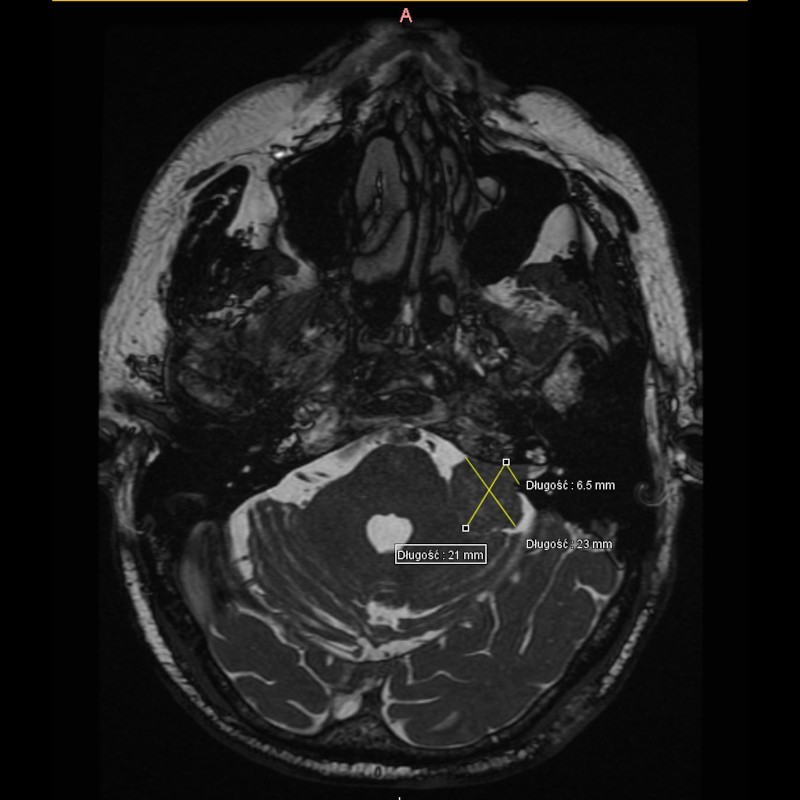

Przed leczeniem (zdj. 1)

W dn. 15.09.2021 do Poradni Radioterapii zgłosił się chory z niedosłuchem lewostronnym i zaburzeniami równowagi. W wyniku MRI głowy w lewym kącie mostowo-móżdżkowym widoczna była lita masa silnie wzmacniającego się guza, który cienką wypustką wpuklał się do światła przewodu słuchowego wew.

Chory został zakwalifikowany do radioterapii stereotaktycznej - CyberKnife. (MRI celem palowania radioterapii - zdj.1)